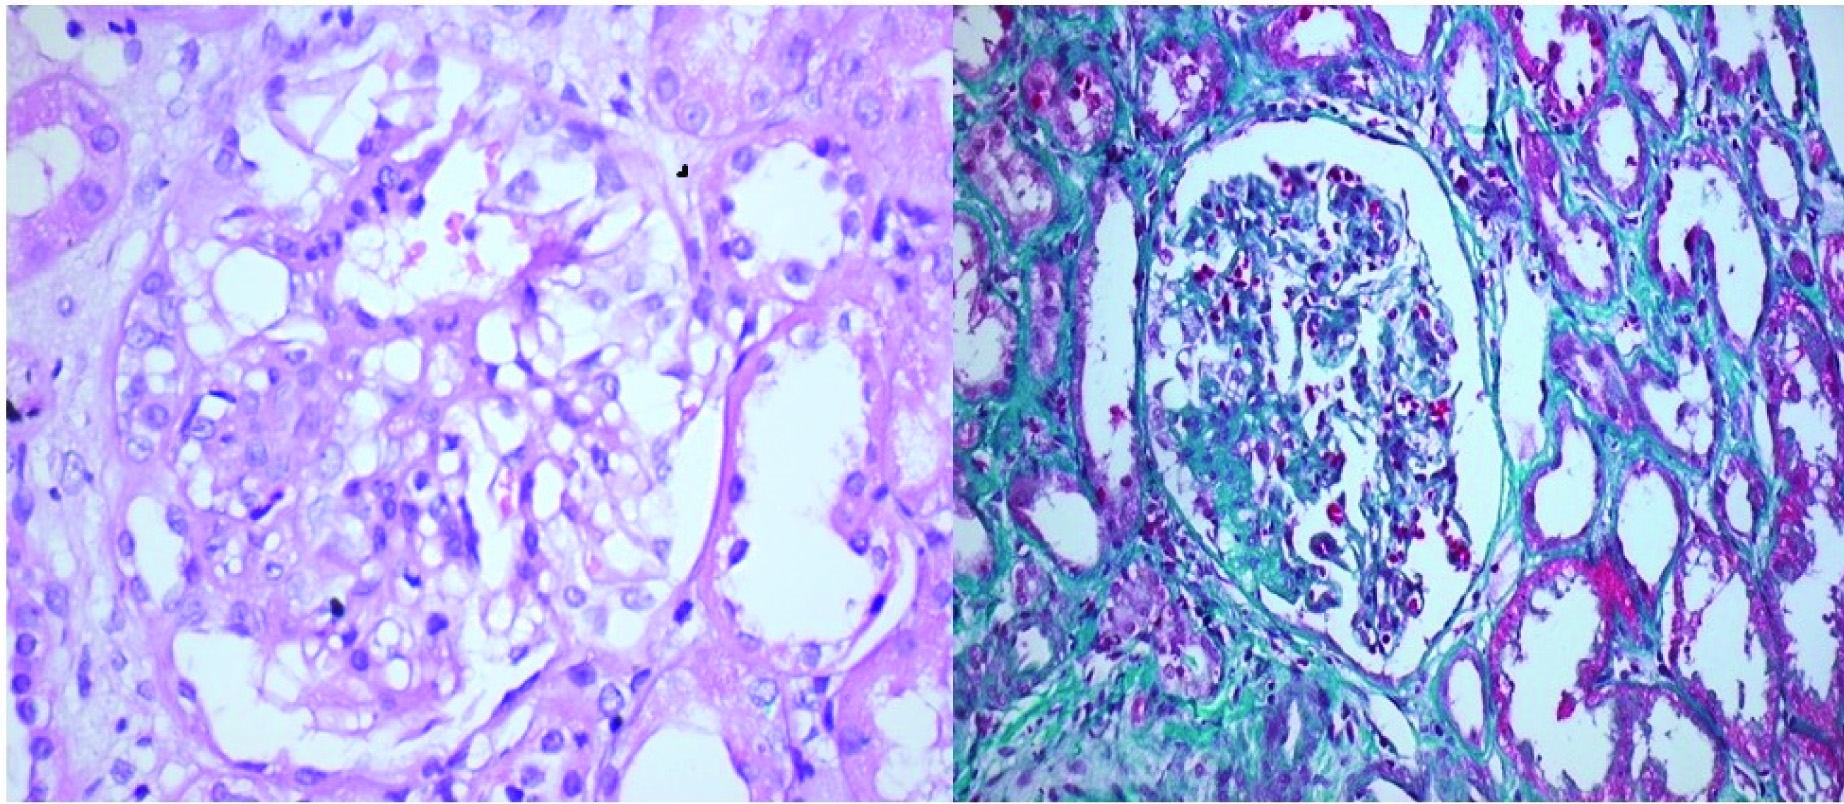

Cellular variant: Only this variant show predominantly endocapillary hypercellularity with occluding capillary lumen with exclusion of tip and collapsing variants [Table/Fig-3a,b].

Cellular variant of FSGS: a) H&E 40X; b) Gomoris’s trichrome 20X (Images from left to right)